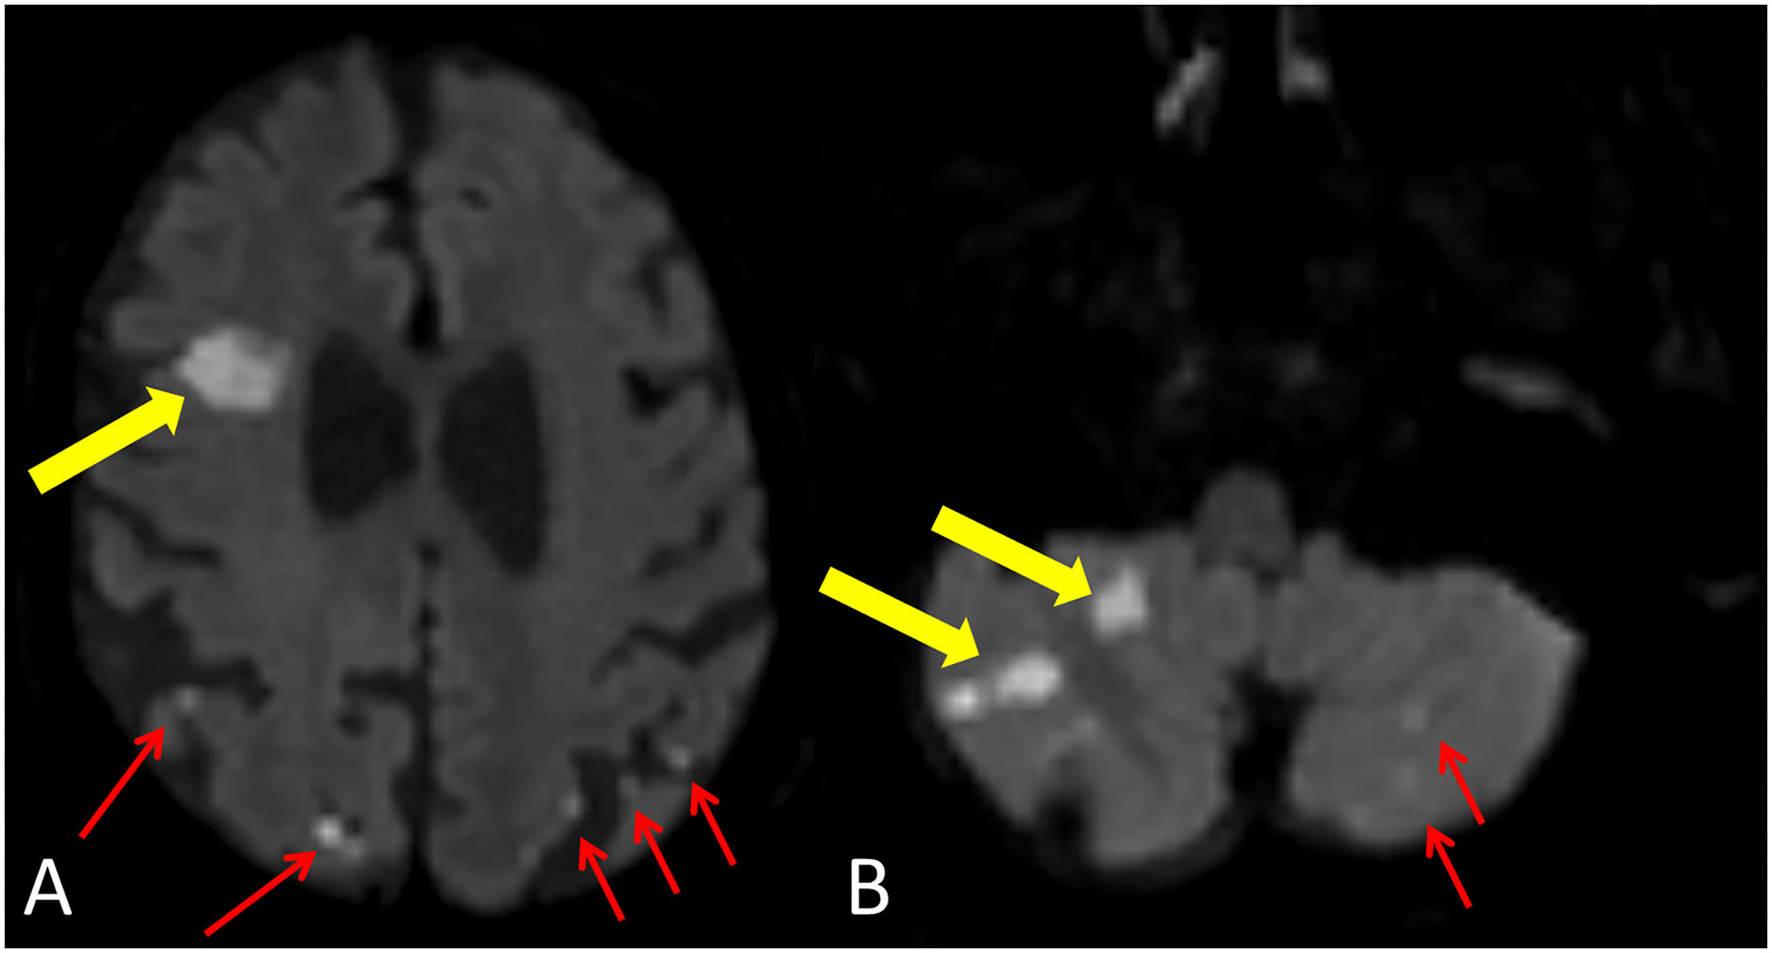

A total of 104 patients (92.0%) had new cerebral ischemic lesions on discharge MRI (Figure 3), among them six patients had periprocedural stroke. The median number of lesions per patient was six (IQR: 2–10), and the median ILV was 257.3 μl (IQR: 97.1–718.8 μl). In addition, 944 new ischemic brain lesions were found on brain MRI, most of the lesions were supratentorial (781/944, 81.9%), and the majority were located in the cortical–subcortical area (796/944, 84.3%). The left and right cerebral and cerebellar hemispheres were equally affected (Table 3). On the 6M MRI, 46/113 (40.7%) patients had gliotic transformation on FLAIR images.

Figure 3

New ischemic lesion after TAVI. Yellow arrows demonstrate a larger lesion with restricted diffusion in the right frontal lobe (A) and in the right cerebellar hemisphere (B). Red arrows show smaller cortical-subcortical lesions with restricted diffusion in the left and right parietal lobes (A) and in the left cerebellar hemisphere (B).